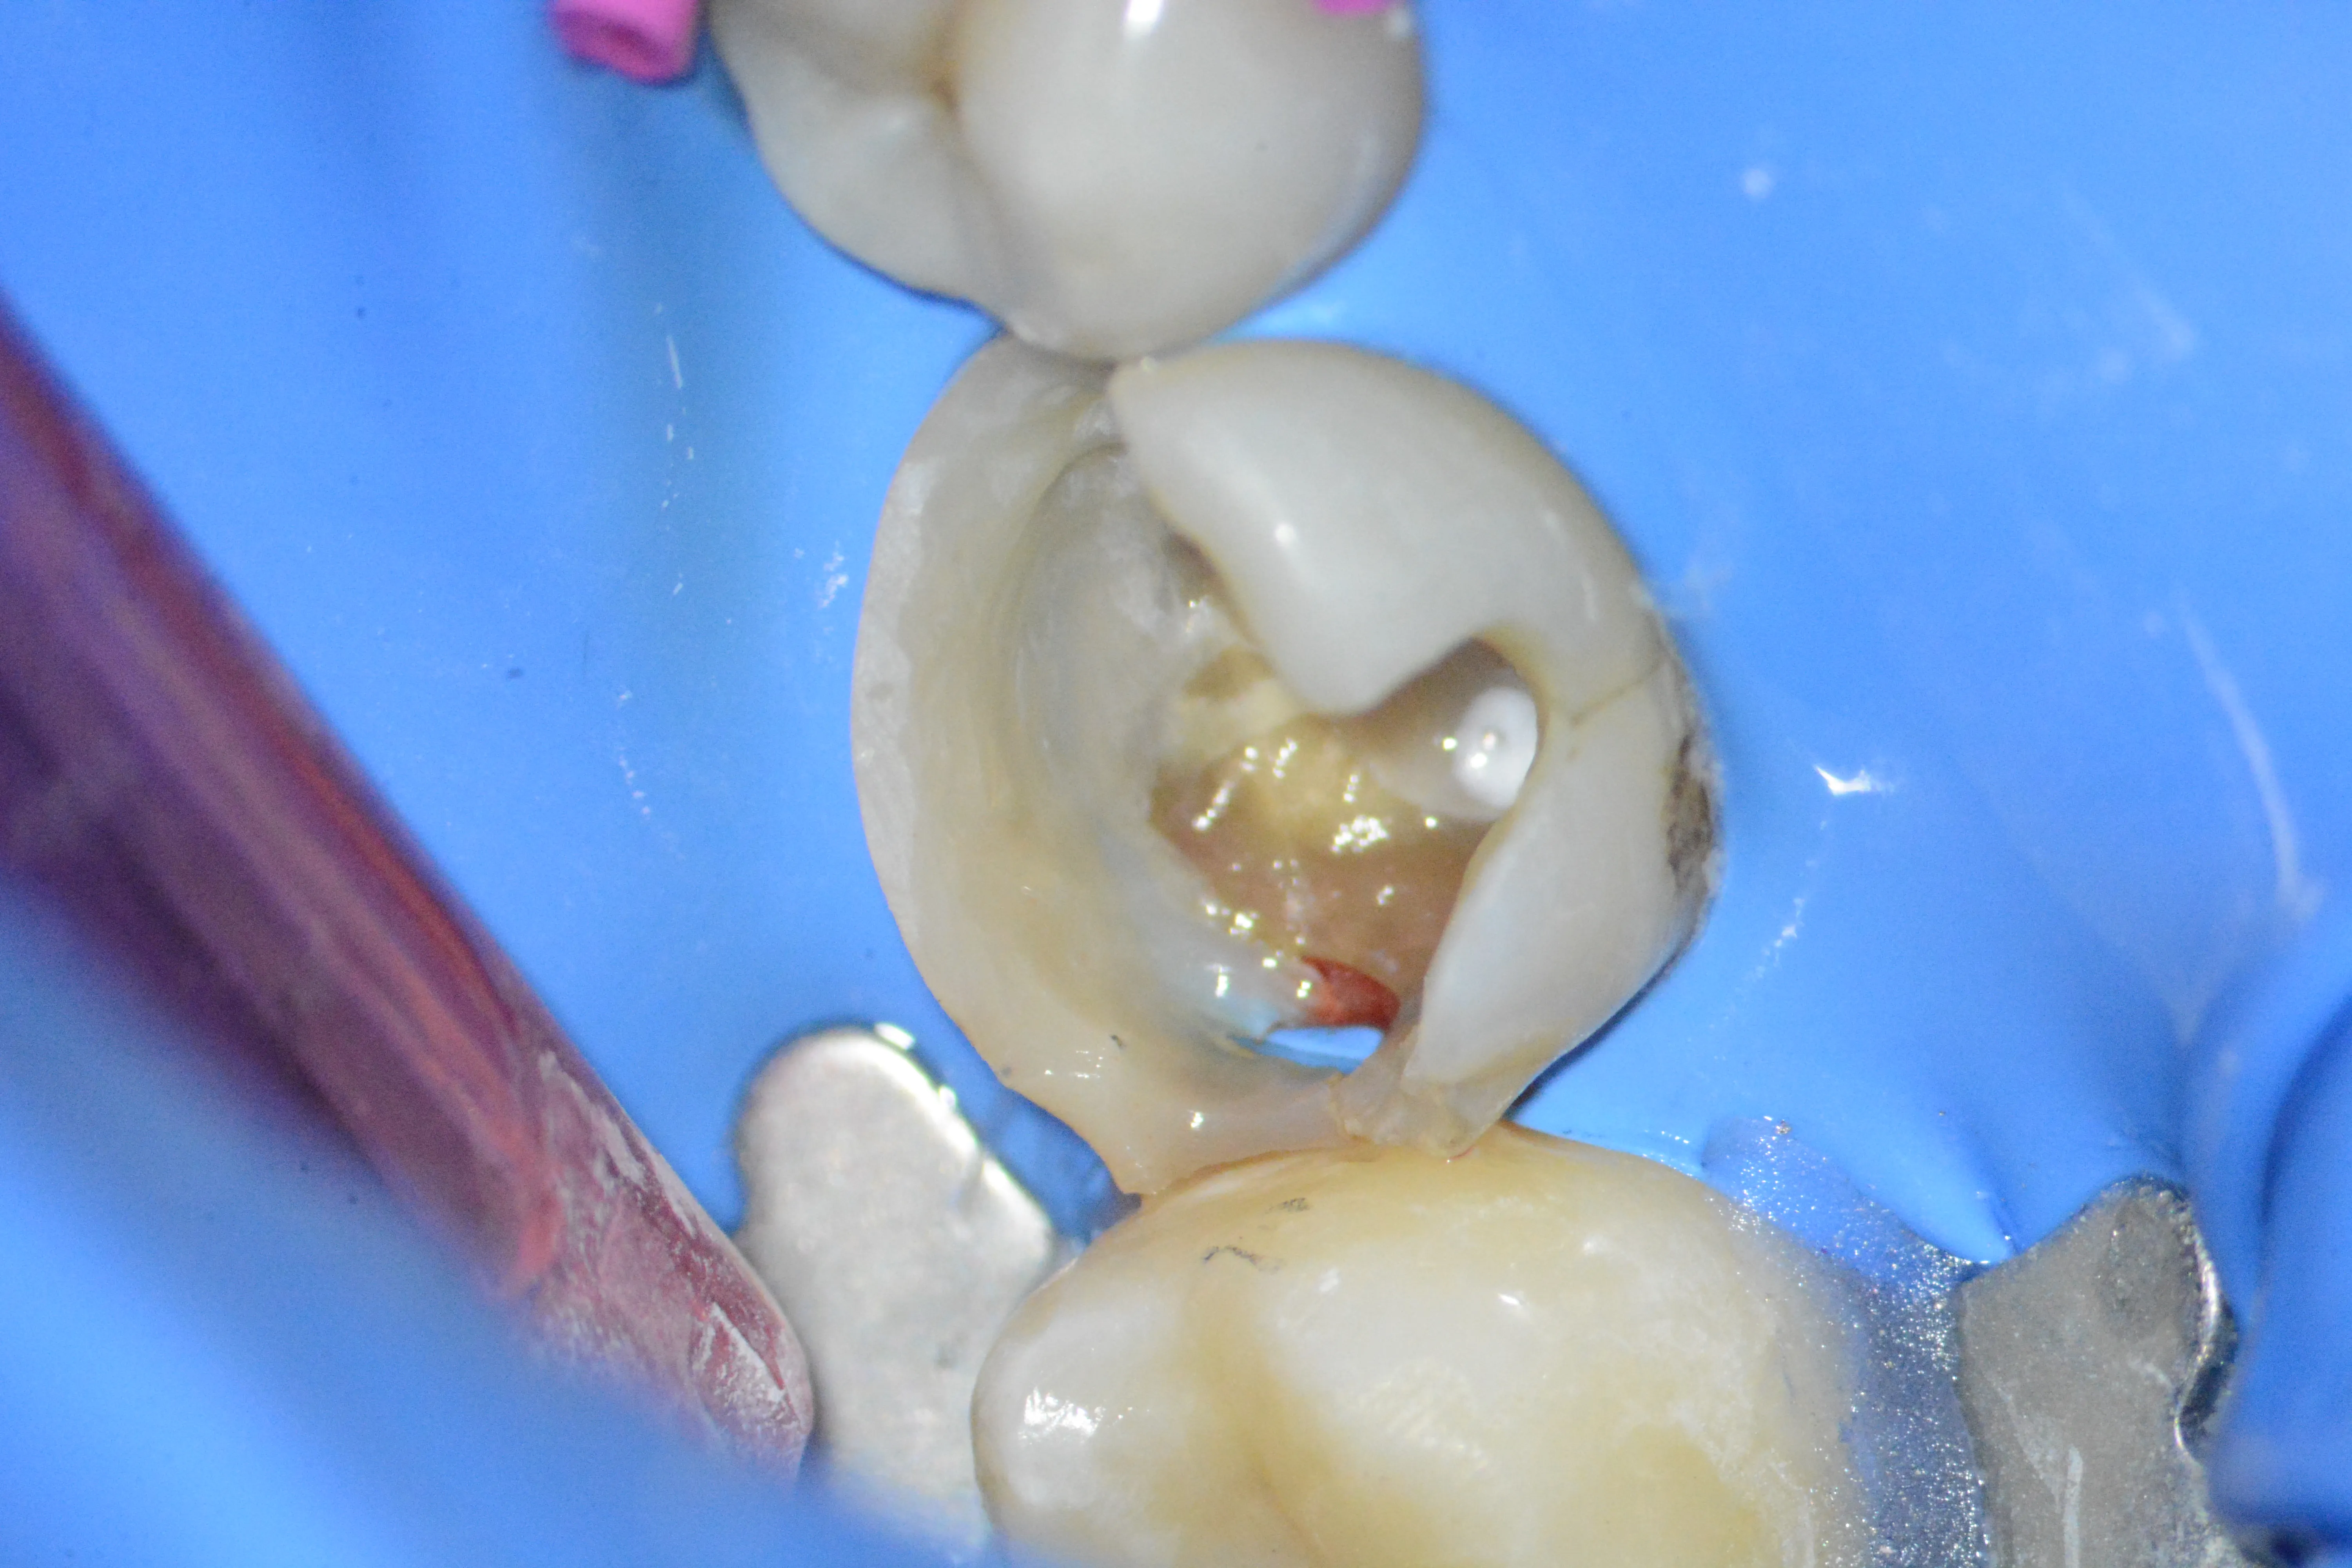

2 – Aspectul după dezasamblarea coronară parțială

5 – Aspectul clinic al orificiilor canalelor radiculare